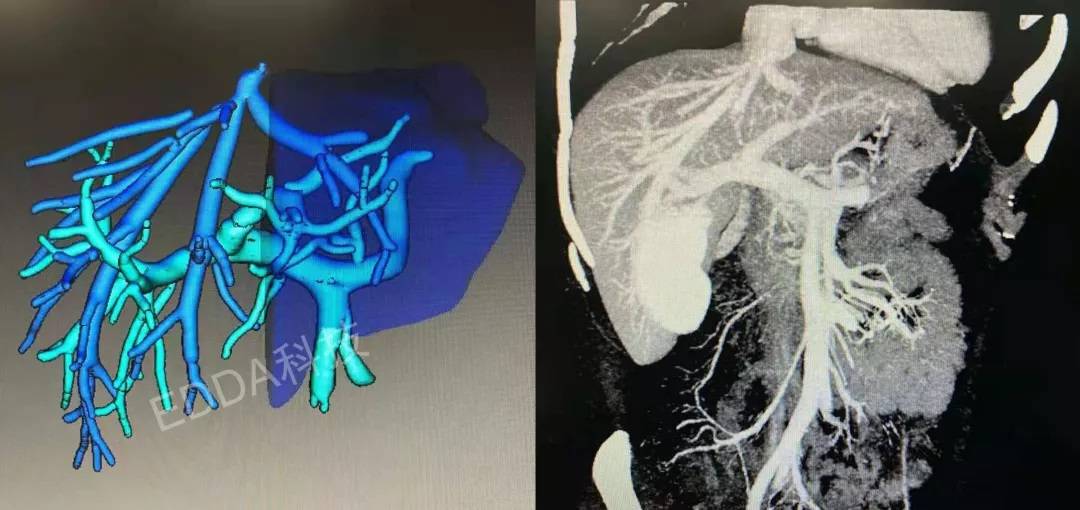

患者177cm、85kg,其子31岁,187cm、92kg,紧急医学评估及伦理审查,发现供者门脉三型,胆道右后叶支汇入左肝管,左半肝仅占全肝26%,右后叶评估690cm3,GRWR大于0.8%,剩余左三肝60%,由其子捐献右后叶肝脏行急症活体肝移植手术,手术过程顺利。